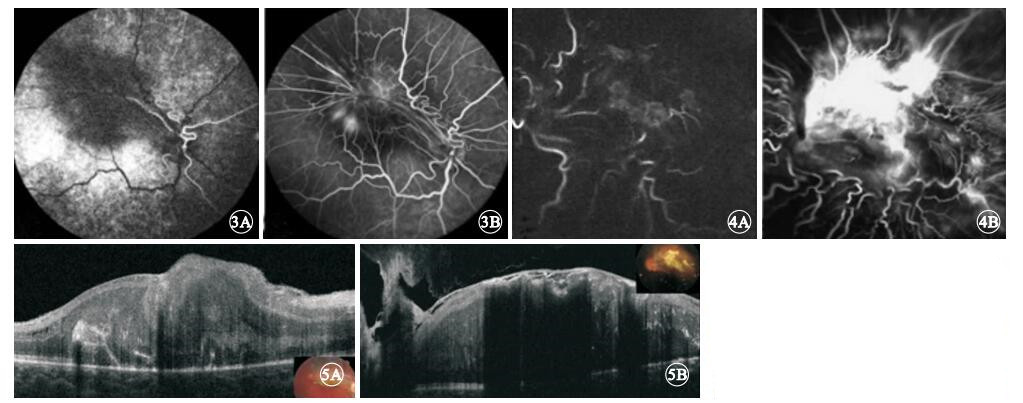

FFA檢查發現,造影早期即可見所有患眼病變部位及其周圍脈絡膜背景熒光均減弱,且其持續存在于整個造影過程中;靜脈期可見因纖維膜收縮、牽引而呈螺旋樣紆曲的視網膜血管走行;病灶處視網膜毛細血管擴張、熒光素滲漏,病變部位熒光亮度逐漸增強(圖 3,4)。均未發現視網膜出血、滲出、毛細血管無灌注區、視網膜新生血管及脈絡膜新生血管等異常。

FFA檢查發現,造影早期即可見所有患眼病變部位及其周圍脈絡膜背景熒光均減弱,且其持續存在于整個造影過程中;靜脈期可見因纖維膜收縮、牽引而呈螺旋樣紆曲的視網膜血管走行;病灶處視網膜毛細血管擴張、熒光素滲漏,病變部位熒光亮度逐漸增強(圖 3,4)。均未發現視網膜出血、滲出、毛細血管無灌注區、視網膜新生血管及脈絡膜新生血管等異常。

FFA檢查發現所有患眼的病變部位脈絡膜背景熒光減弱,我們認為這與瘤體及其周圍沉著的色素對背景熒光遮蔽有關。由于CHRRPE病灶表面有纖維膜增生,這些纖維膜不斷收縮,造成被其牽引的視網膜血管呈現不同程度的紆曲。這些異常走行的血管因其表面有纖維膜覆蓋,部分血管在彩色眼底像上難于被分辨,而FFA檢查可清晰顯示這些血管的走行。通過對比彩色眼底像及FFA像,我們發現纖維膜增生最為致密處視網膜血管紆曲最為顯著。提示FFA檢查也是評價CHRRPE病灶表面纖維膜分布的重要檢查手段。除導致視網膜血管紆曲外,FFA檢查還發現所有CHRRPE病灶表面均有擴張的視網膜毛細血管,在造影過程中,這些擴張的毛細血管滲漏熒光素,導致病變部位熒光亮度增強。但視網膜毛細血管擴張、滲漏的病理現象究竟是與瘤體不斷產生炎性介質導致正常血管通透性增強,即所謂的“炎癥繼發CHRRPE學說”[3]有關或是與纖維膜機械牽拉導致視網膜血管壁受損有關仍需進一步探討。有研究表明,借助FFA檢查可發現CHRRPE病灶內存在的視網膜微動脈瘤、新生血管、滋養血管及脈絡膜新生血管,而周邊視網膜走行變直、變細、無血管區及新生血管也可在造影過程中被發現[5, 6]。但本研究結果顯示,所有患眼除視網膜血管扭曲外,均未發生毛細血管無灌注區及新生血管。這可能與本研究樣本量較小有關。

FFA檢查發現所有患眼的病變部位脈絡膜背景熒光減弱,我們認為這與瘤體及其周圍沉著的色素對背景熒光遮蔽有關。由于CHRRPE病灶表面有纖維膜增生,這些纖維膜不斷收縮,造成被其牽引的視網膜血管呈現不同程度的紆曲。這些異常走行的血管因其表面有纖維膜覆蓋,部分血管在彩色眼底像上難于被分辨,而FFA檢查可清晰顯示這些血管的走行。通過對比彩色眼底像及FFA像,我們發現纖維膜增生最為致密處視網膜血管紆曲最為顯著。提示FFA檢查也是評價CHRRPE病灶表面纖維膜分布的重要檢查手段。除導致視網膜血管紆曲外,FFA檢查還發現所有CHRRPE病灶表面均有擴張的視網膜毛細血管,在造影過程中,這些擴張的毛細血管滲漏熒光素,導致病變部位熒光亮度增強。但視網膜毛細血管擴張、滲漏的病理現象究竟是與瘤體不斷產生炎性介質導致正常血管通透性增強,即所謂的“炎癥繼發CHRRPE學說”[3]有關或是與纖維膜機械牽拉導致視網膜血管壁受損有關仍需進一步探討。有研究表明,借助FFA檢查可發現CHRRPE病灶內存在的視網膜微動脈瘤、新生血管、滋養血管及脈絡膜新生血管,而周邊視網膜走行變直、變細、無血管區及新生血管也可在造影過程中被發現[5, 6]。但本研究結果顯示,所有患眼除視網膜血管扭曲外,均未發生毛細血管無灌注區及新生血管。這可能與本研究樣本量較小有關。